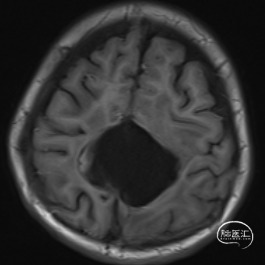

双侧额顶叶中线旁脑实质内团片状异常信号影,呈明显花环状强化,累积脑膜及胼胝体压部,性质待定,恶性胶质瘤?

非典型畸胎瘤样/横纹肌样瘤( AT /RT) 是发生在儿童中枢神经系统的少见的具有极大侵袭性的恶性肿瘤,在儿童中枢神经系统肿瘤中发病率极低。CT平扫多表现为混杂密度,也可等或稍高密度,呈不均匀或均匀强化,瘤内常可见囊性变及瘤周低密度水肿带。MRI扫描T1加权像为低信号,T2加权像为等信号或高信号,肿瘤实质与灰质信号相似或稍高,增强扫描可见中等至明显 增强,等信号时可能与肿瘤细胞密集,细胞核比例大而含水量相对较少有关。AT /RT是原发于中枢神经系统、好发于儿童、极其少见、侵袭性极高的胚胎性肿瘤,临床表 现及影像学无特异性,确诊有赖于组织病理。最大限度的安全切除,并辅以放化疗,可改善患者预后,但总体预后仍然很差。